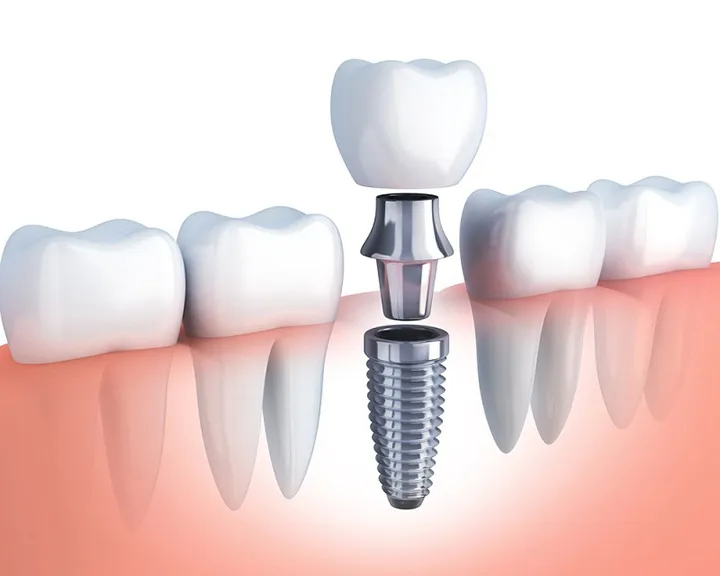

Cơ sở máy móc điều trị nha khoa hiện đại

Một cơ sở nha khoa tốt sẽ được trang bị đầy đủ máy móc, thiết bị hiện đại nhất, đáp ứng trong việc chẩn đoán bệnh và điều trị bệnh hiệu quả. Một số máy móc có thể kể đến như: máy CT 3D, máy chụp x-quang, máy cạo vôi siêu âm… Sử dụng máy móc hiện đại sẽ giúp nha sĩ đưa ra chẩn đoán bệnh chính xác, rút ngắn thời gian điều trị, giảm đau đớn cho người bệnh, hiệu quả cao.